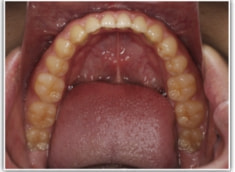

開咬(かいこう:オープンバイト)ケース

治療法:表の矯正(T21ブラケット)

(インプラントアンカーや外科矯正は行わず、エラスティックと機能訓練のみ)

治療前